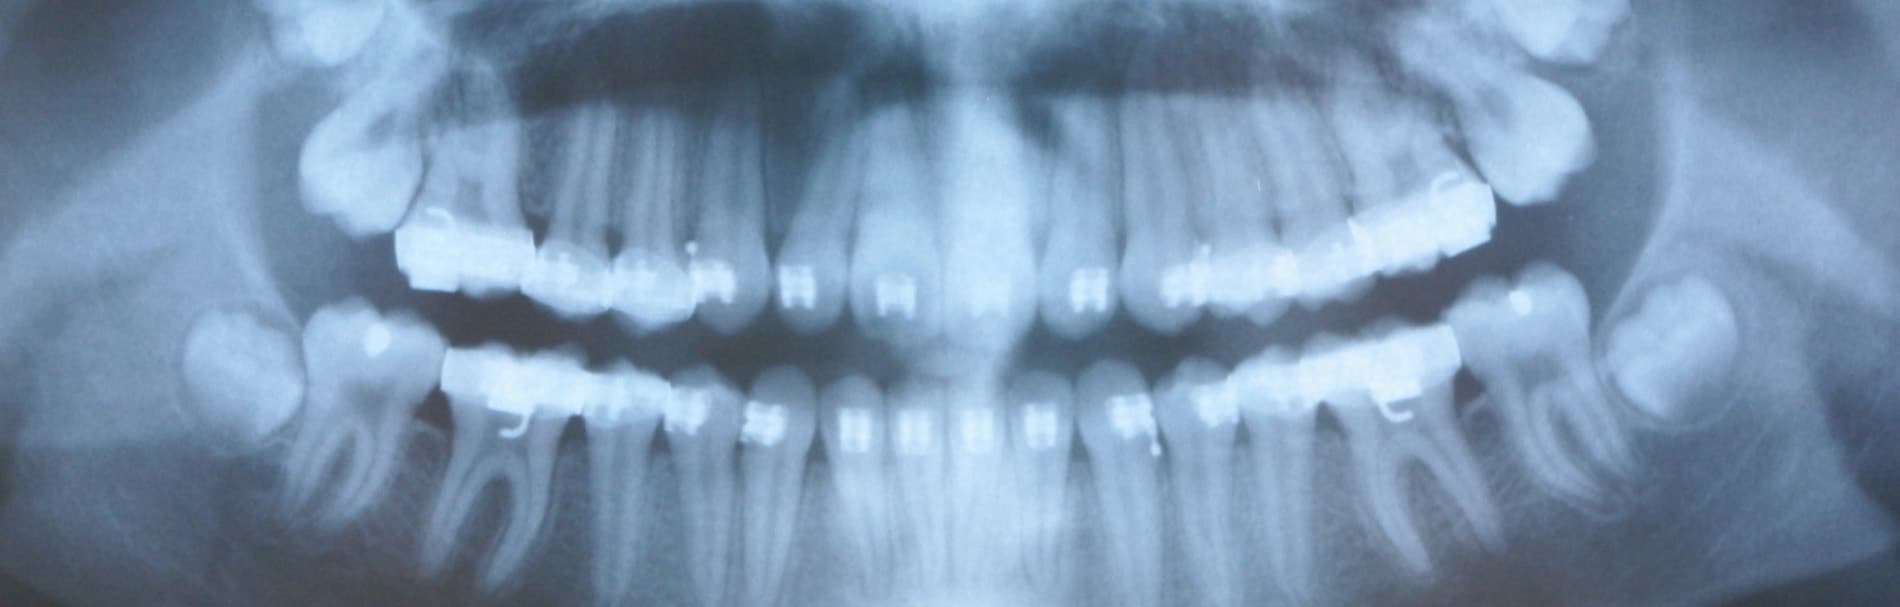

OPG

Met behulp van een grote overzichtsröntgenfoto beoordeelt de tandarts het aantal en de ligging van de tanden en kiezen en de grootte en vorm van de wortels en de kaken. De officiële naam van deze foto is orthopantomogram, afgekort OPG. Deze foto is onder meer van belang om te bepalen, wanneer het beste met een (ortho)behandeling kan worden gestart. Op dergelijke foto’s is nog veel meer te zien. Zo kan men o.a. nagaan of alle tanden en kiezen zijn aangelegd. Vaak wordt ook een OPG gemaakt om te kijken, of er voldoende kaakbot aanwezig is om implantaten te plaatsen.